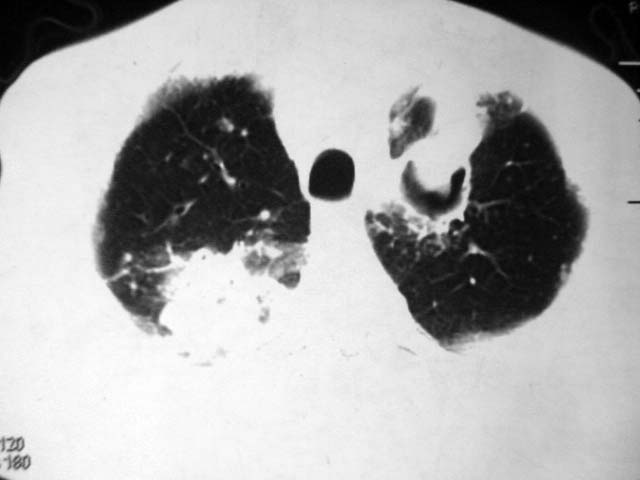

2、双肺见多发片状及结节状高密度影,大多数病灶中心均见“空泡征”。

结果:两肺继发性肺结核并曲霉菌感染。